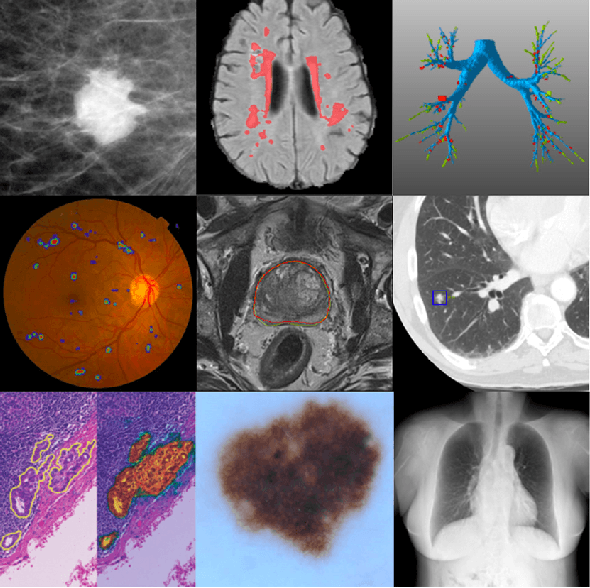

In the past ten years, with the help of deep learning, especially the rapid development of deep neural networks, medical image analysis has made remarkable progress. However, how to effectively use the relational information between various tissues or organs in medical images is still a very challenging problem, and it has not been fully studied. In this thesis, we propose two novel solutions to this problem based on deep relational learning. First, we propose a context-aware fully convolutional network that effectively models implicit relation information between features to perform medical image segmentation. The network achieves the state-of-the-art segmentation results on the Multi Modal Brain Tumor Segmentation 2017 (BraTS2017) and Multi Modal Brain Tumor Segmentation 2018 (BraTS2018) data sets. Subsequently, we propose a new hierarchical homography estimation network to achieve accurate medical image mosaicing by learning the explicit spatial relationship between adjacent frames. We use the UCL Fetoscopy Placenta dataset to conduct experiments and our hierarchical homography estimation network outperforms the other state-of-the-art mosaicing methods while generating robust and meaningful mosaicing result on unseen frames.